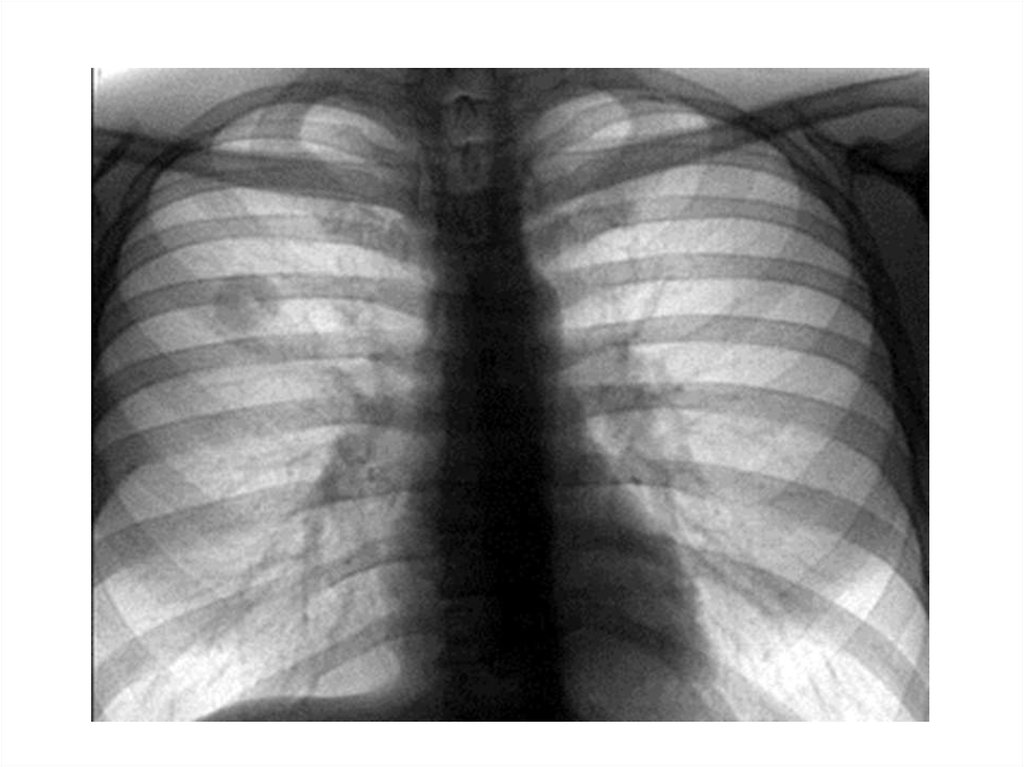

Туберкулема легких

1. Туберкулема легких